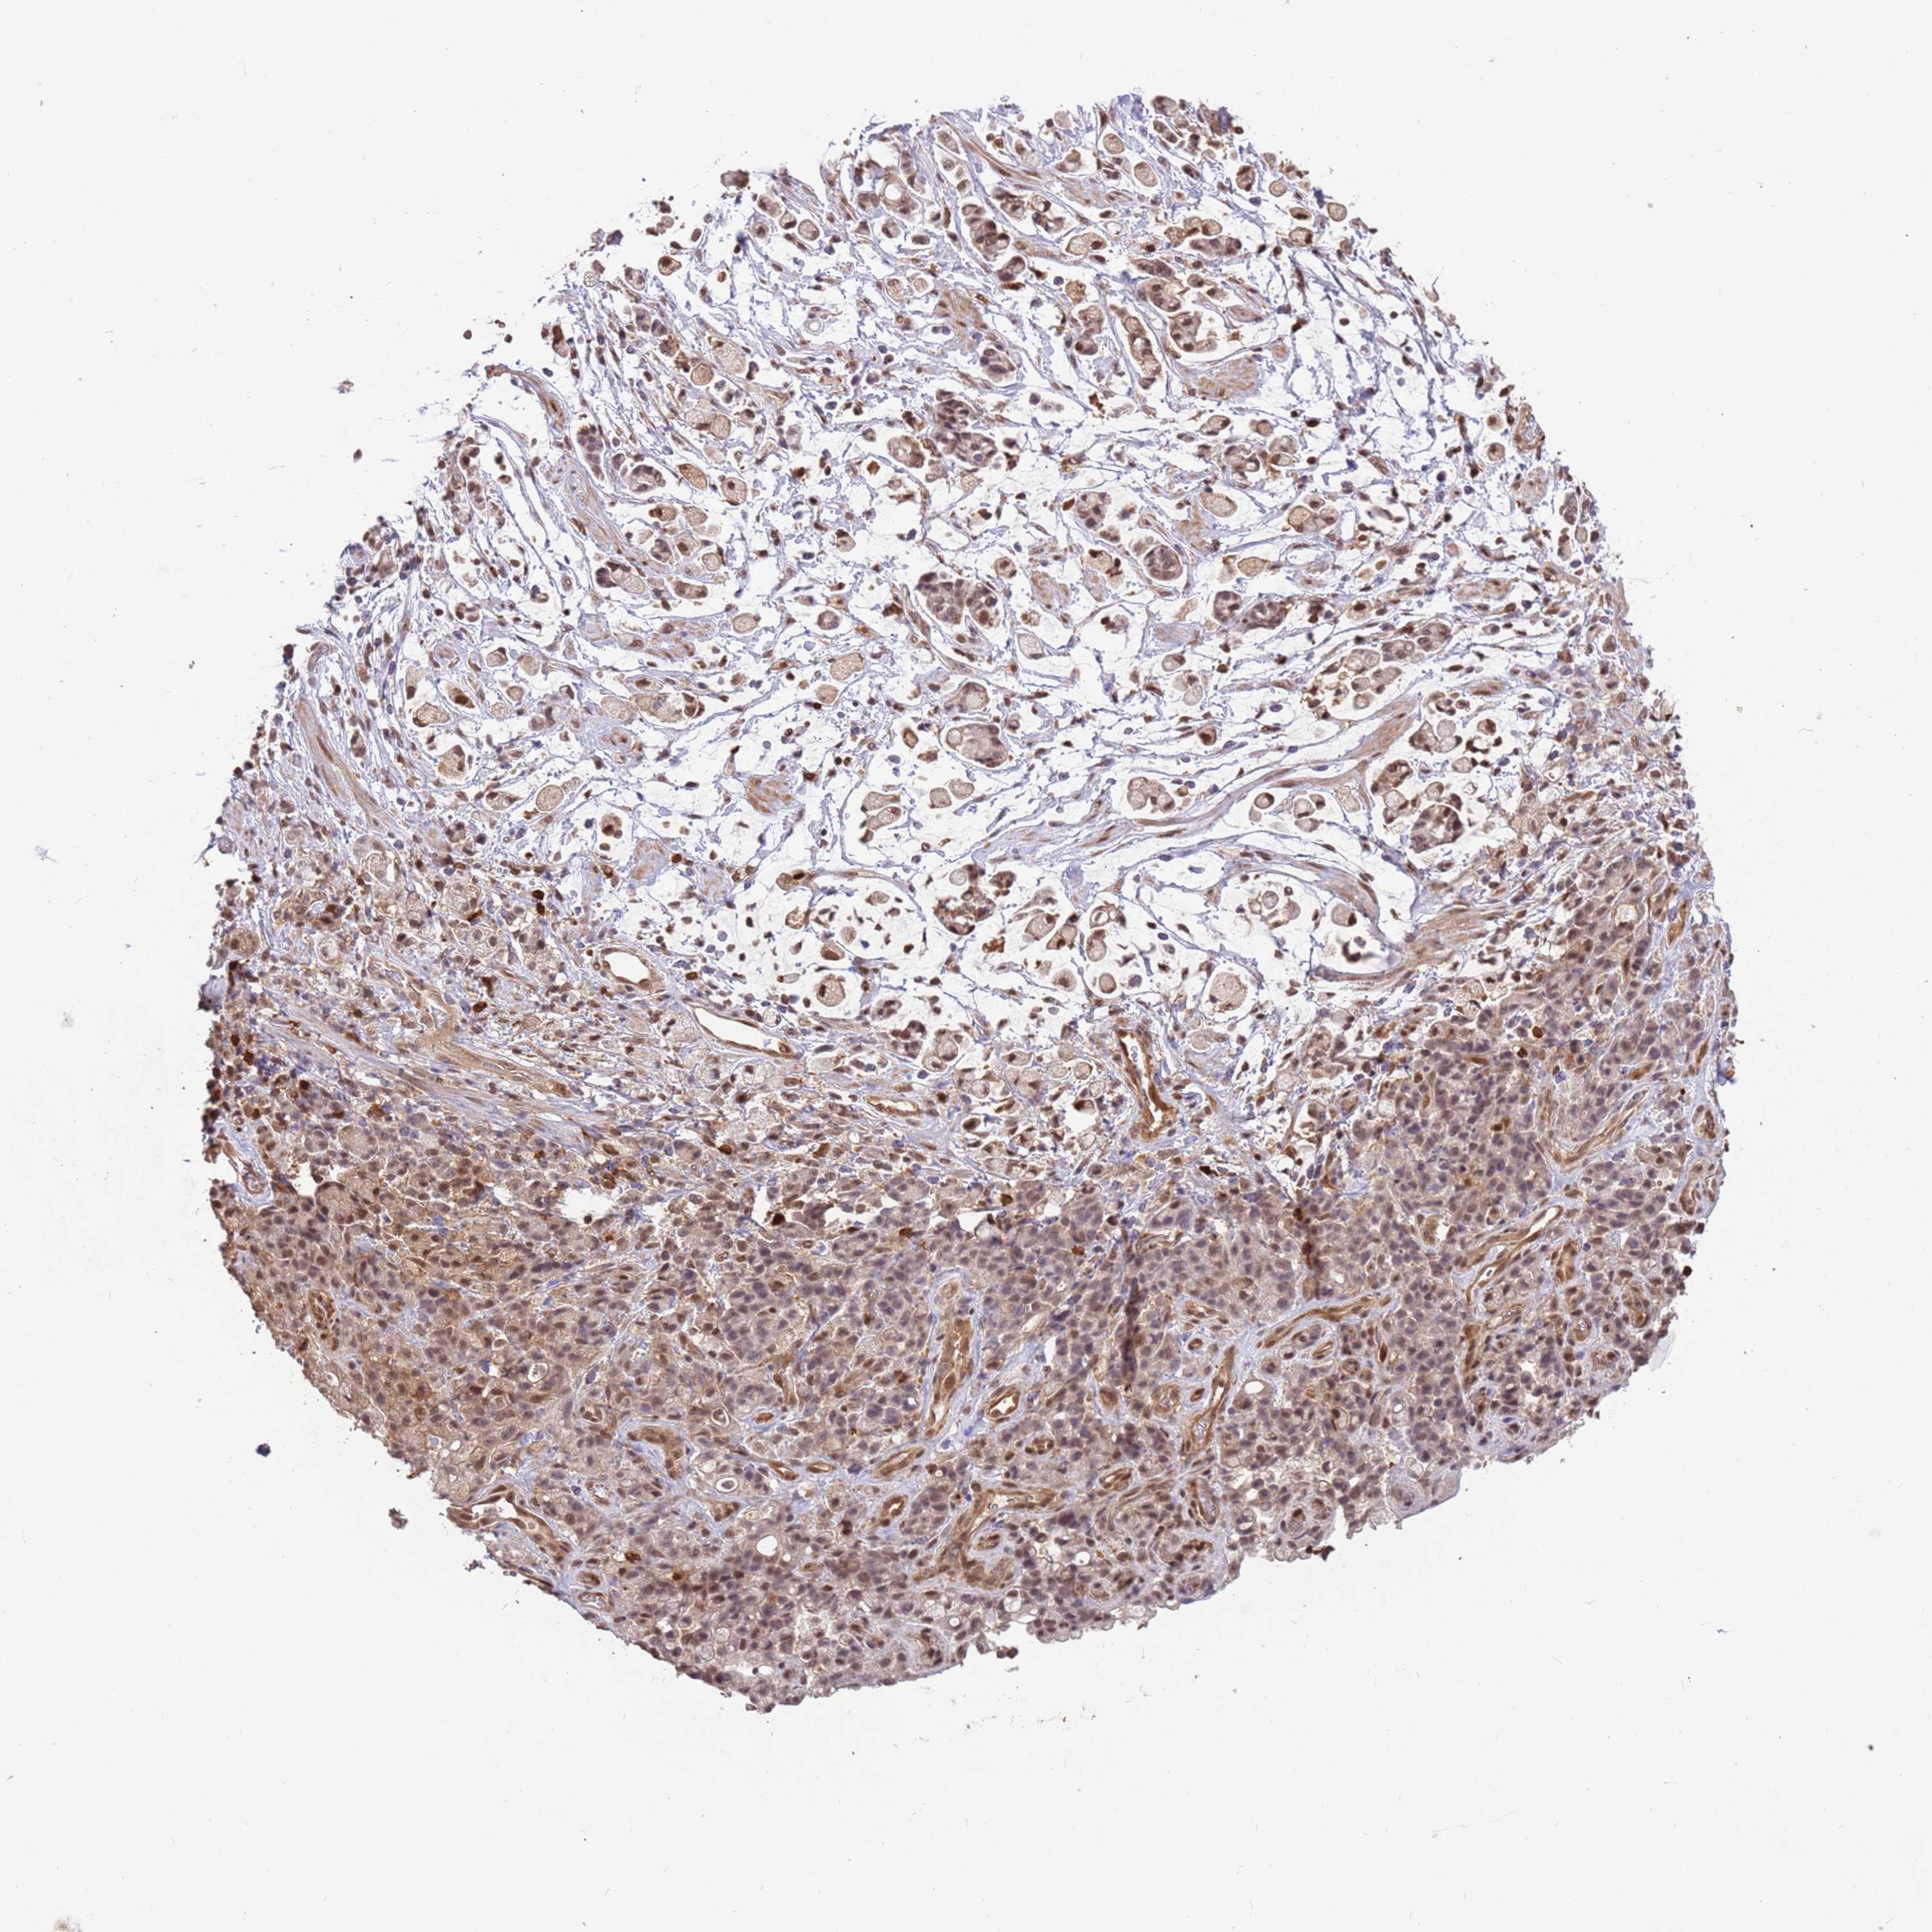

STOMACH CANCER - Protein expressioni

A mouse-over function shows sample information and annotation data. Click on an image to view it in a full screen mode. Samples can be filtered based on level of antibody staining by selecting one or several of the following categories: high, medium, low and not detected. The assay and annotation is described here.

Note that samples used for immunohistochemistry by the Human Protein Atlas do not correspond to samples in the TCGA dataset.

Antibody stainingi

Antibody staining in the annotated cell types in the current human tissue is reported as not detected, low, medium, or high, based on conventional immunohistochemistry profiling in selected tissues. This score is based on the combination of the staining intensity and fraction of stained cells.

Each image is clickable and will lead to virtual microscopy that enables deeper exploration of all samples and also displays staining intensity scores, fraction scores and subcellular localization as well as patient and tissue information for each sample.

Antibody HPA042682

Antibody CAB045975

Staining

High

Medium

Low

Not detected

Intensity

Strong

Moderate

Weak

Negative

Quantity

>75%

75%-25%

<25%

None

Location

Nuclear

Cytoplasmic/membranous

Cytoplasmic/membranous,nuclear

Adenocarcinoma, NOS